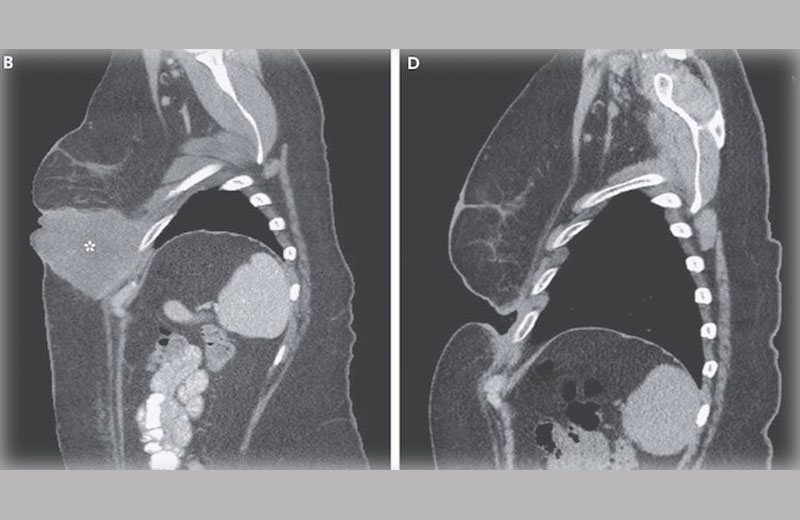

A equipe também descobriu que o medicamento potencial reduziu muito tumores especificamente nos pulmões de ratos que tinham sido injetados com células de melanoma humano.